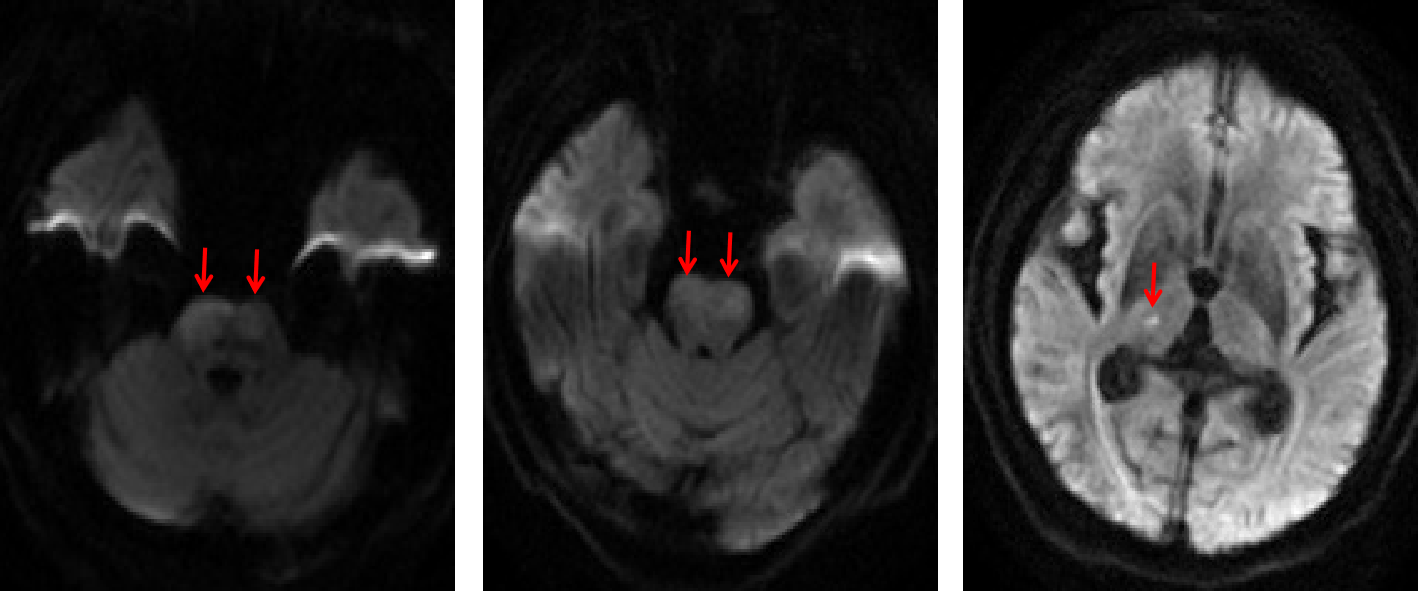

患者已处于重度昏迷。神经内科介入小组(高震主治医师、瞿慧阳医师、张倩护士和蒋鹏鹏护士)和当天值班二线李燕玲主治医师第一时间赶到现场,协同完成术前准备并推入导管室。消毒-铺巾-穿刺-超选-打药,脑血管造影显示患者大脑前部血管均为烟雾血管,没有主干,唯一赖以生存的椎基底动脉完全堵塞。

图2 颈动脉末端闭塞,血管呈烟雾样表现,椎基底动脉堵塞

患者命悬一线,刚刚结束一天工作的王虎清教授,用最短时间评估并制定了手术方案。家属态度积极,签字同意手术。高震主治医师和瞿慧阳医师采用经典的抽拉结合动脉取栓(SWIM术式)和球囊扩张技术在20分钟内实现了闭塞的基底动脉完美再通。

图3 采用经典抽拉结合动脉取栓(SWIM术式)和球囊扩张技术在20分钟内实现了基底动脉闭塞完美再通